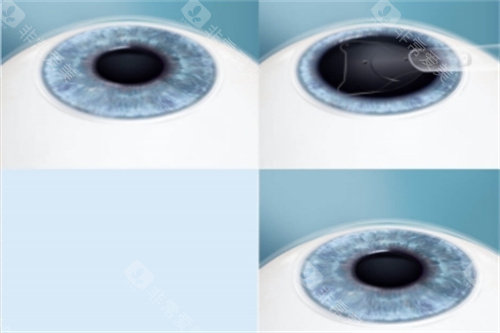

3. 飞秒辅助ICL(智臻飞秒ICL)

飞秒ICL(基础版):3.36万~3.7万元/双眼(郑州爱尔眼科3.36万元起)

飞秒TICL(散光版):3.76万~4.1万元/双眼(郑州爱尔眼科3.76万元起)

追求更高精密度的患者

手术方式:飞秒辅助ICL比传统ICL贵6000~8000元。